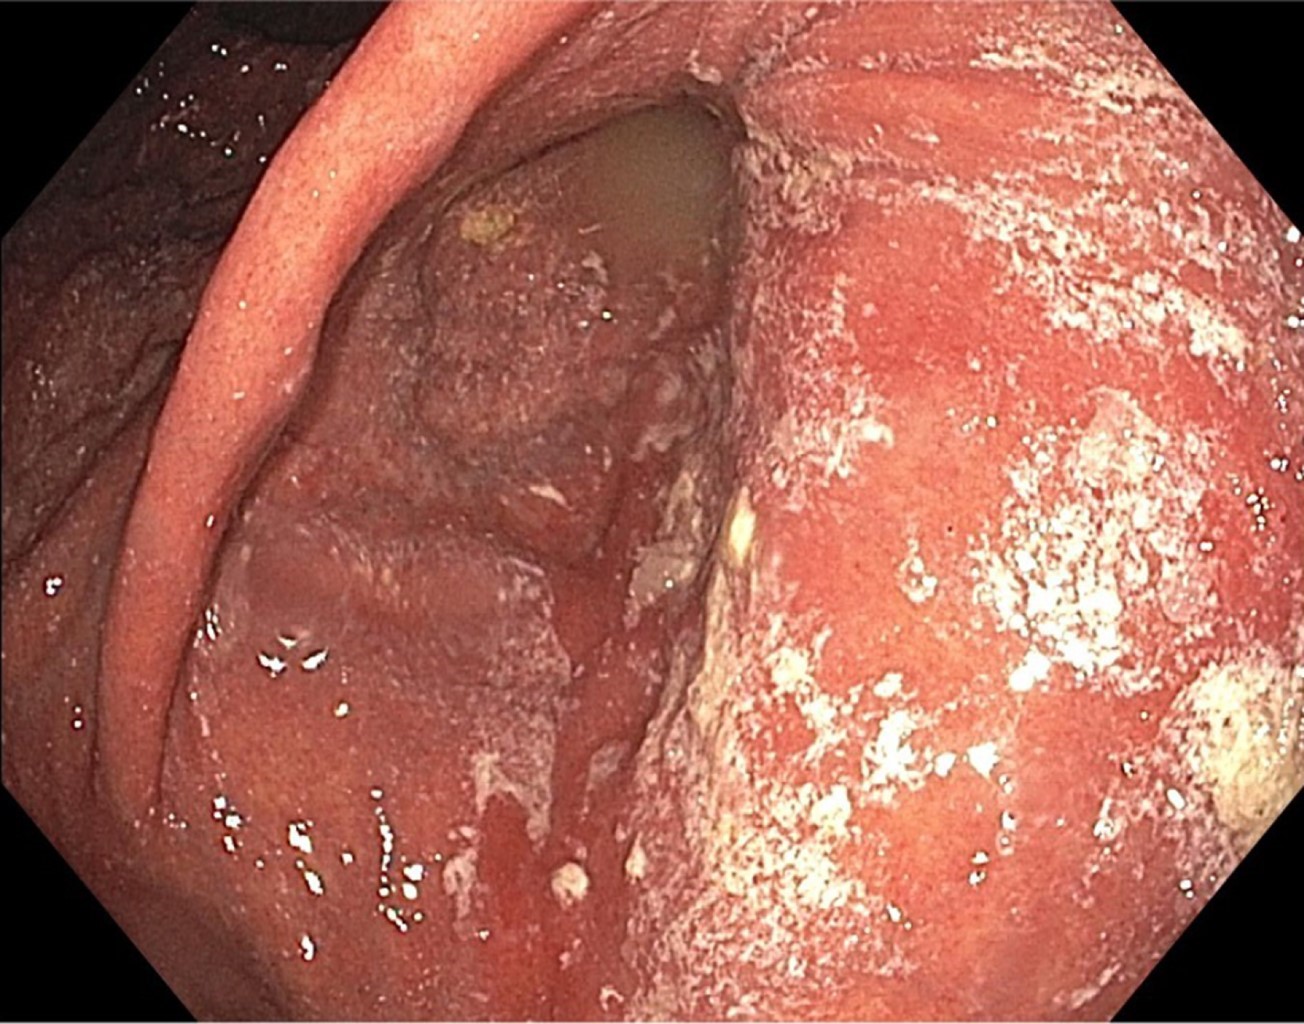

El paciente fue hospitalizado y se le efectuó tomografía toracoabdominal, que reportó al estómago con engrosamiento de sus pliegues y signo de remolino hacia la región del píloro, confirmando la sospecha diagnóstica (Figura 2), por lo que se optó por la resolución quirúrgica urgente mediante laparoscopía, detorsión gástrica y gastropexia (Figuras 3 y 4). La evolución fue satisfactoria; un esofagograma con medio hidrosoluble de control posquirúrgico confirmó la ausencia de complicaciones a las 12 horas de la cirugía y el paciente pudo egresar para seguimiento por consulta externa tras cuatro días de estancia hospitalaria (Figura 5).

Por tratarse de una entidad infrecuente, su diagnóstico requiere de alta sospecha clínica.3-5 La confirmación suele llevarse a cabo mediante métodos radiológicos como los estudios contrastados o la tomografía toracoabdominal, siendo esta última, además, capaz de identificar defectos anatómicos y evidenciar la presencia de perforaciones.3,9

Dentro de las múltiples opciones con las que se cuentan hoy en día, los estudios radiológicos desempeñan un papel importante, la tomografía abdominal permite caracterizar el vólvulo gástrico y detectar si hay complicaciones asociadas, ya que los cortes menores a 1 mm permiten la reconstrucción de las imágenes con excelente calidad.

Figura 2